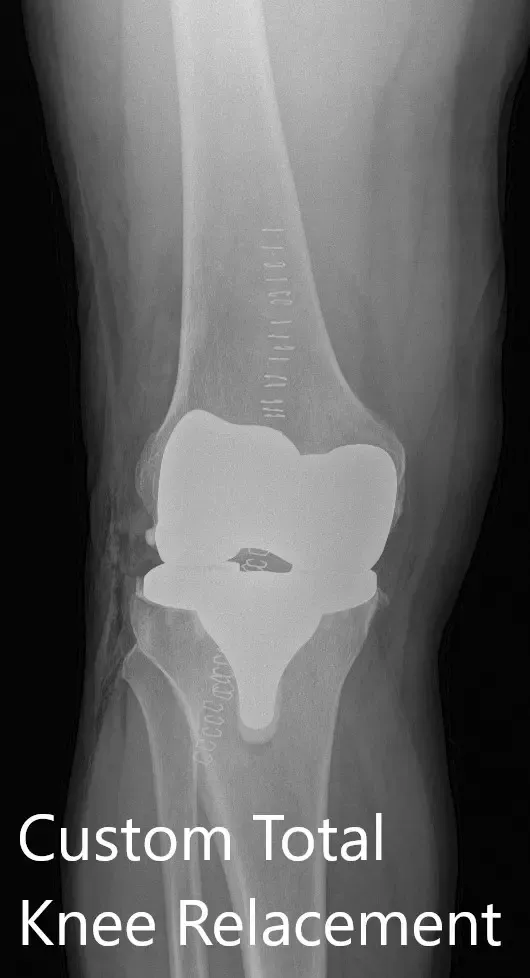

IMPLANTS USED: Custom femoral implant with a 6 mm polyethylene inserts with a custom tibial implant with a patella of size 38 mm, 8.5 mm.

Complete Orthopedics patient-specific surgical plan for a customized right knee replacement in a 65-year-old female.